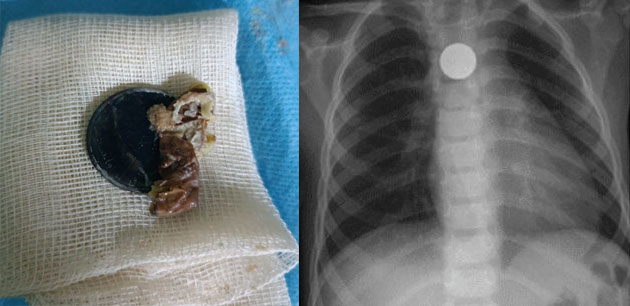

تمكن فريق طبي بمستشفى الاختصاصات بوكافر، التابع للمركز الاستشفائي الإقليمي بورزازات، الخميس 17 غشت 2023، من استخراج عملة معدنية كان قد ابتلعها طفل ينحدر من إقليم تنغير ويبلغ من العمر ثلاث سنوات.

ونجح الفريق الطبي المكون من الدكتور بنباخ محمد، طبيب مختص في أمراض الأنف والحنجرة والأذن، ودكتور "أخصائي في الإنعاش والتخدير"، التحق بمستشفى بوكافر في الأشهر القليلة الماضية، وذلك بموجب اتفاقية شراكة أبرمتها المندوبية الإقليمية للصحة والحماية والاجتماعية بورزازات، تهدف إلى تعزيز المؤسسات الصحية بإقليم ورزازات بالأطر الطبية الجديدة، (نجح) من انتزاع العملة المعدنية عبر إجراء عملية جراحية ناجحة للطفل.

هذا، ورغم أن الفريق الطبي المُشرف على هذه العملية، لم يستقبل الطفل المريض، إلا بعد مرور 20 يوما من ابتلاعه للقطعة المعدنية، فقد نجح في استخراج هذه العملة النقدية، دونما مضاعفات.